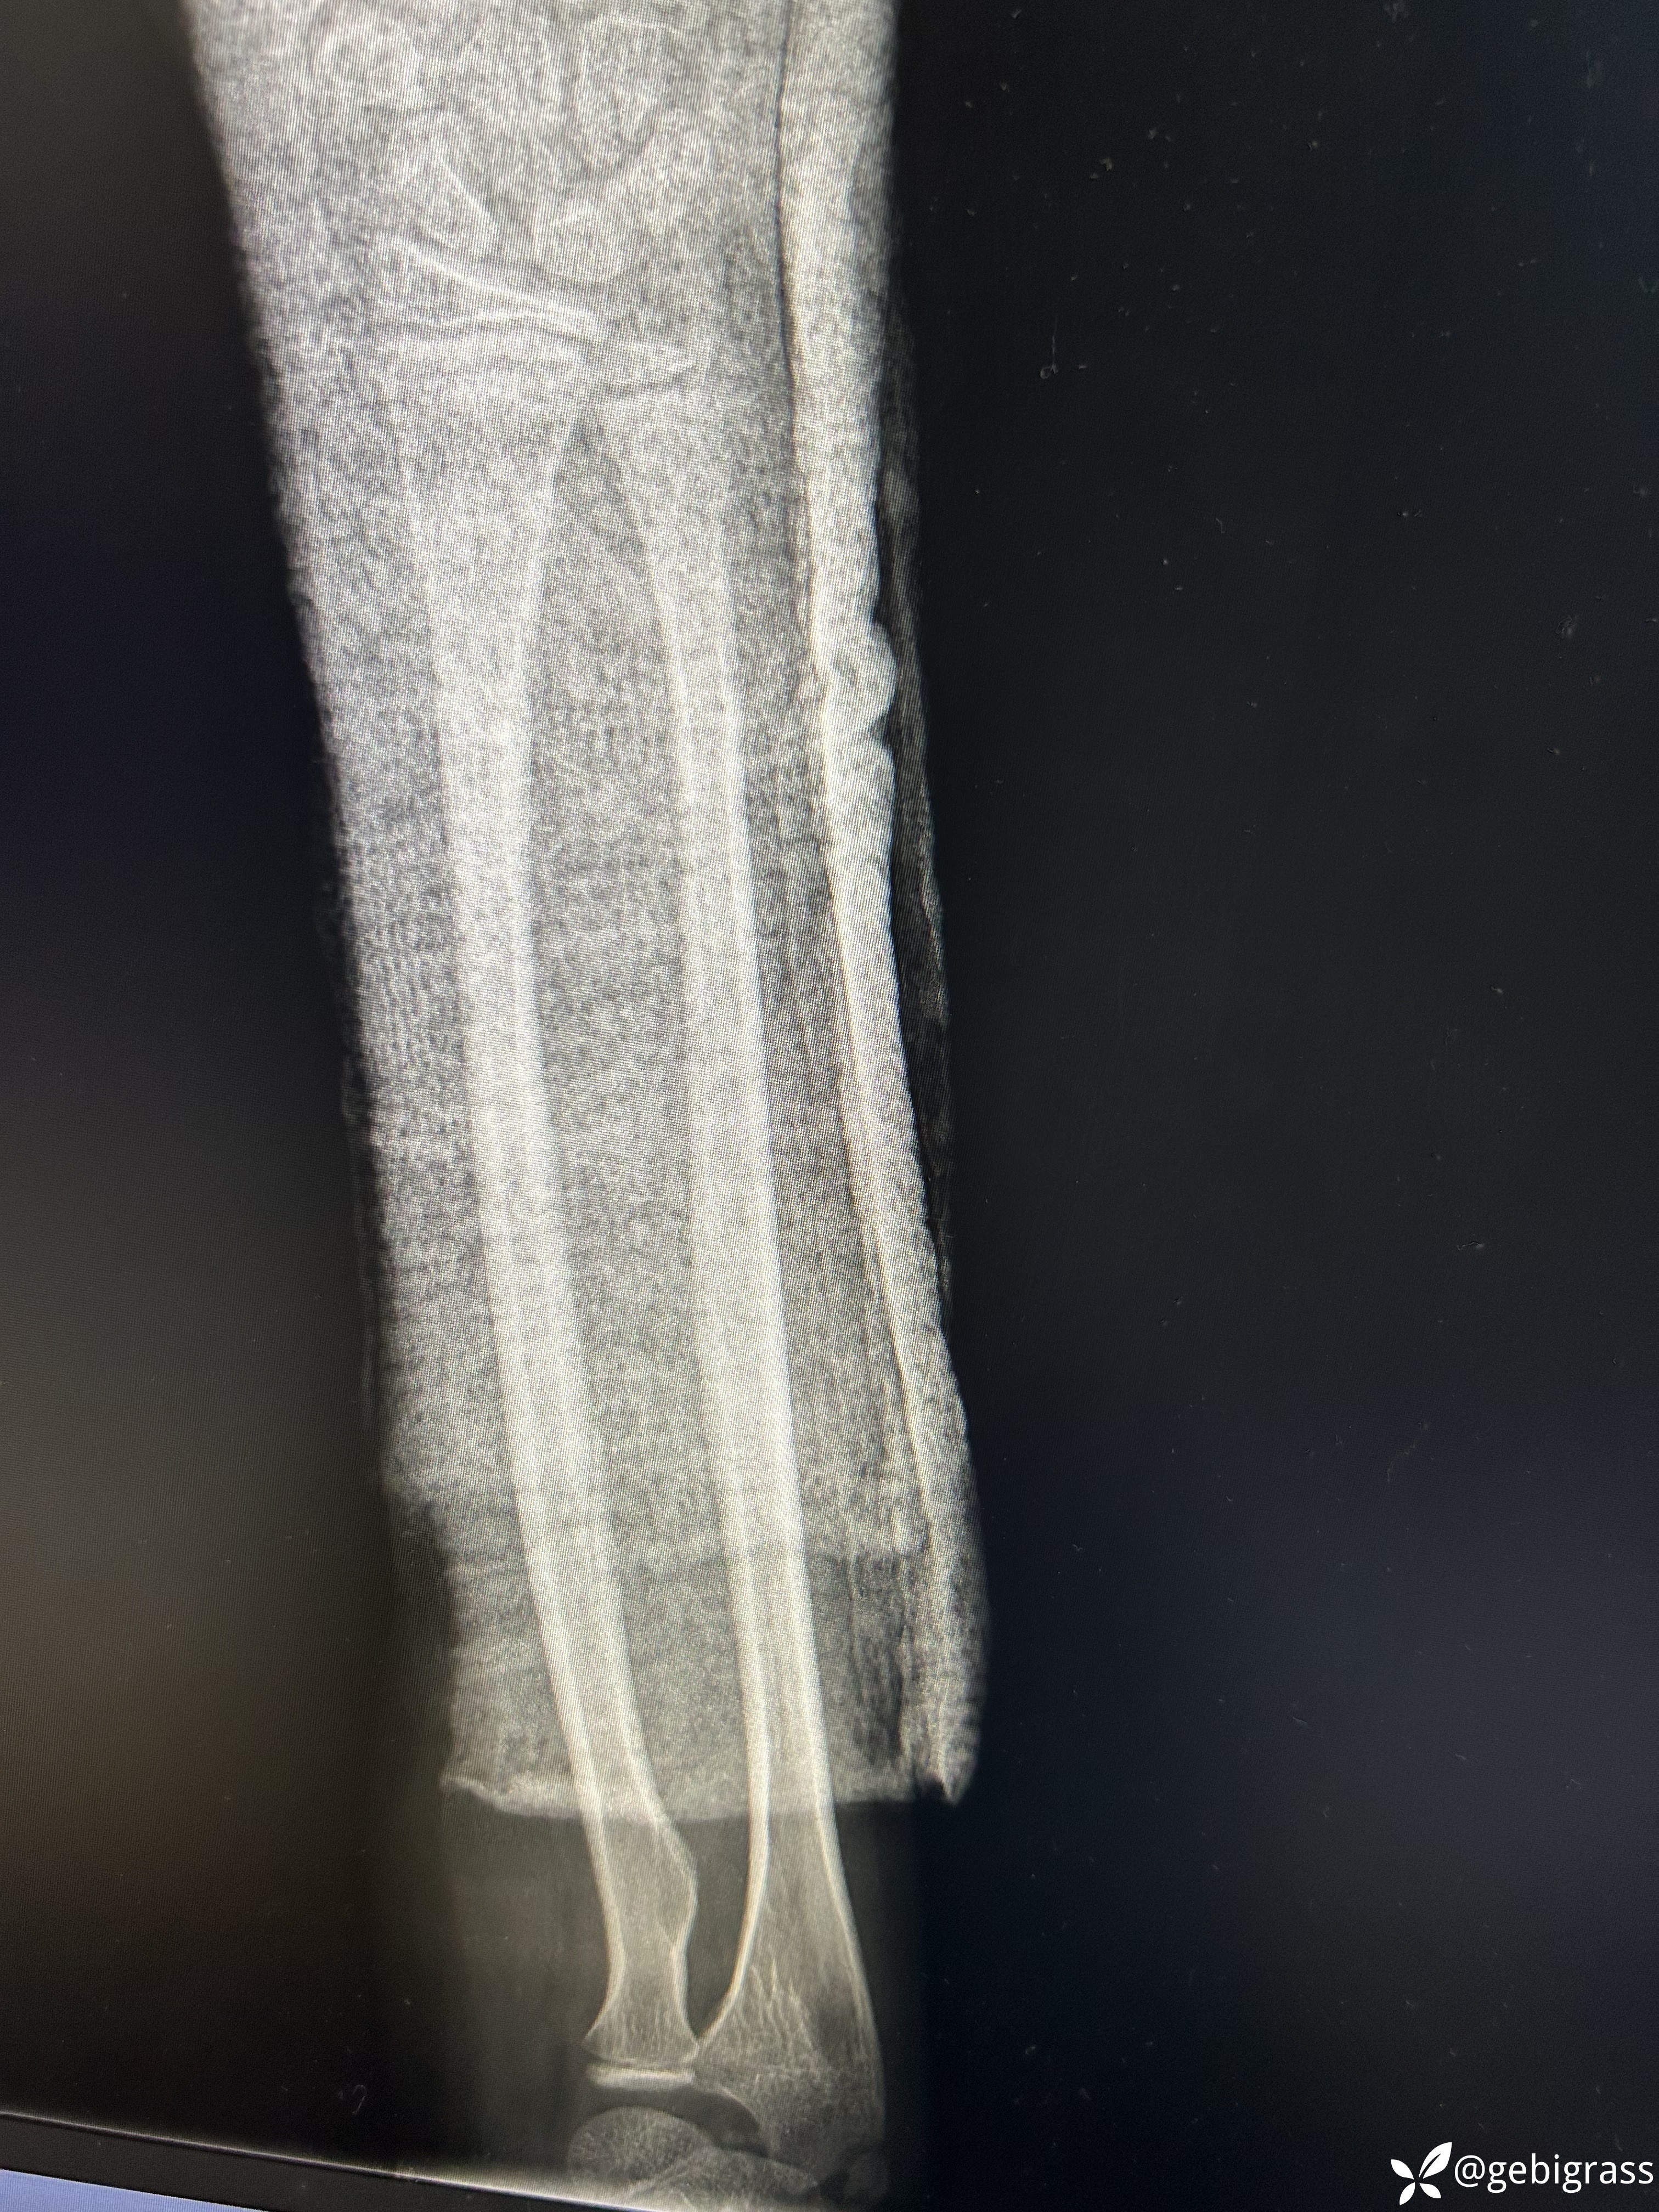

复位后: